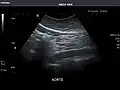

Aorta: Visualized portions normal in caliber, 16 x 15 mm.

Aorta -

It can be used on the abdominal aorta to detect or exclude abdominal aortic aneurysm. For this purpose, the standard aortic measurement for abdominal aortic aneurysm is between the outer margins of the aortic wall.[4]